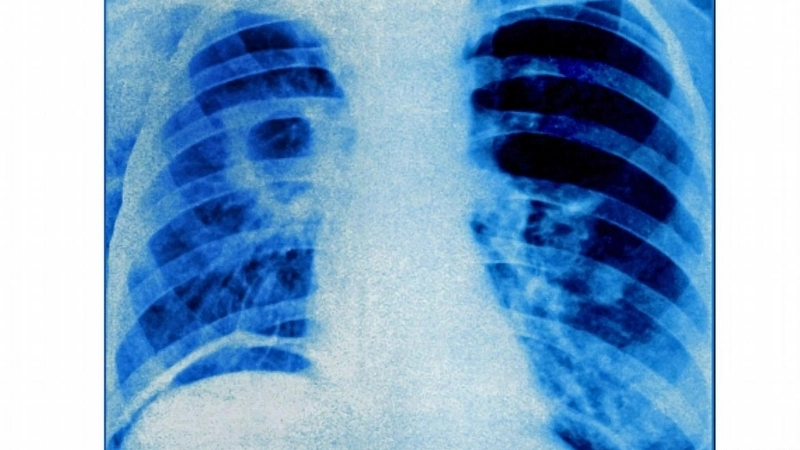

Hình ảnh phổi của người bị lao ở giai đoạn đầu